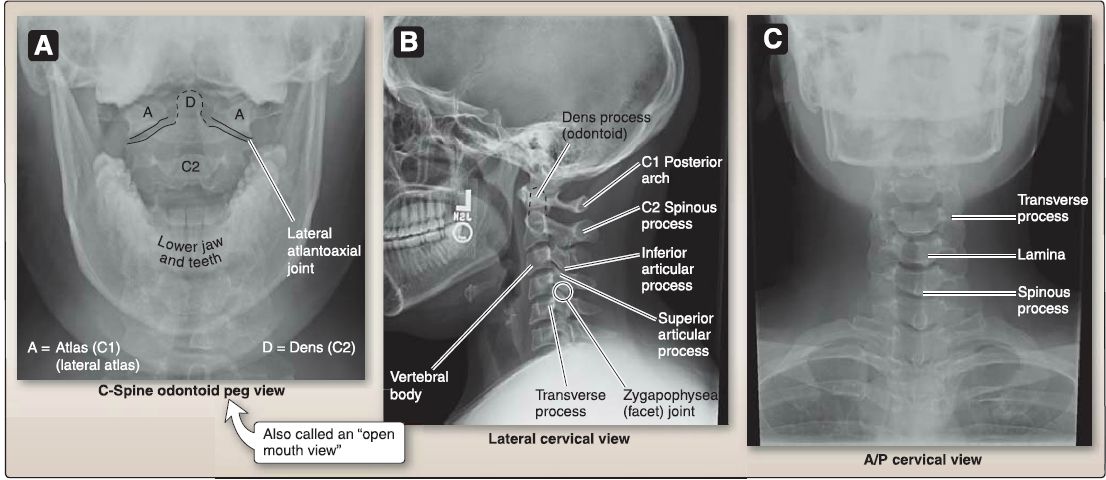

1. Cervical (C1-C7): As shown in Figures 3 and 4, cervical vertebrae feature a small body and a large, triangular vertebral foramen. A foramen transversarium in the transverse processes accommodates vertebral vessels and sympathetic plexuses. Articular processes are oriented in the horizontal (transverse) plane. Spinous processes in C3-C5 are short and bifid (divided into two equal parts). Unique cervical vertebrae are described as follows.

a. C1 (atlas): This ring-like vertebra has neither body nor spinous process. It articulates with occipital condyles through two lateral masses (atlanto-occipital joint) and has a small anterior facet for articulation with the dens (odontoid process) of C2.

b. C2 (axis): This vertebra is strong, featuring a dens that projects superiorly to articulate with C1 (pivot joint).

c. C7 (vertebra prominens): This vertebra with its long, prominent spinous process makes a reliable surface landmark.

Figure 3: A, Atlas (C1) and axis (C2). B, Cervical vertebrae features.

Figure 4: Cervical plain film views (A-C).